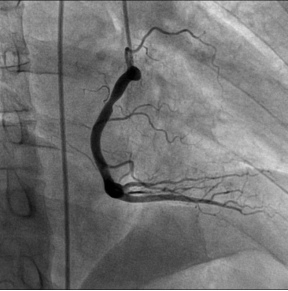

上图:病患右颈内动脉造影显示大脑中动脉

有动脉瘤

病患的右冠狭窄 DSA支架植入 右冠状动脉恢复正常供血,病人病情缓解